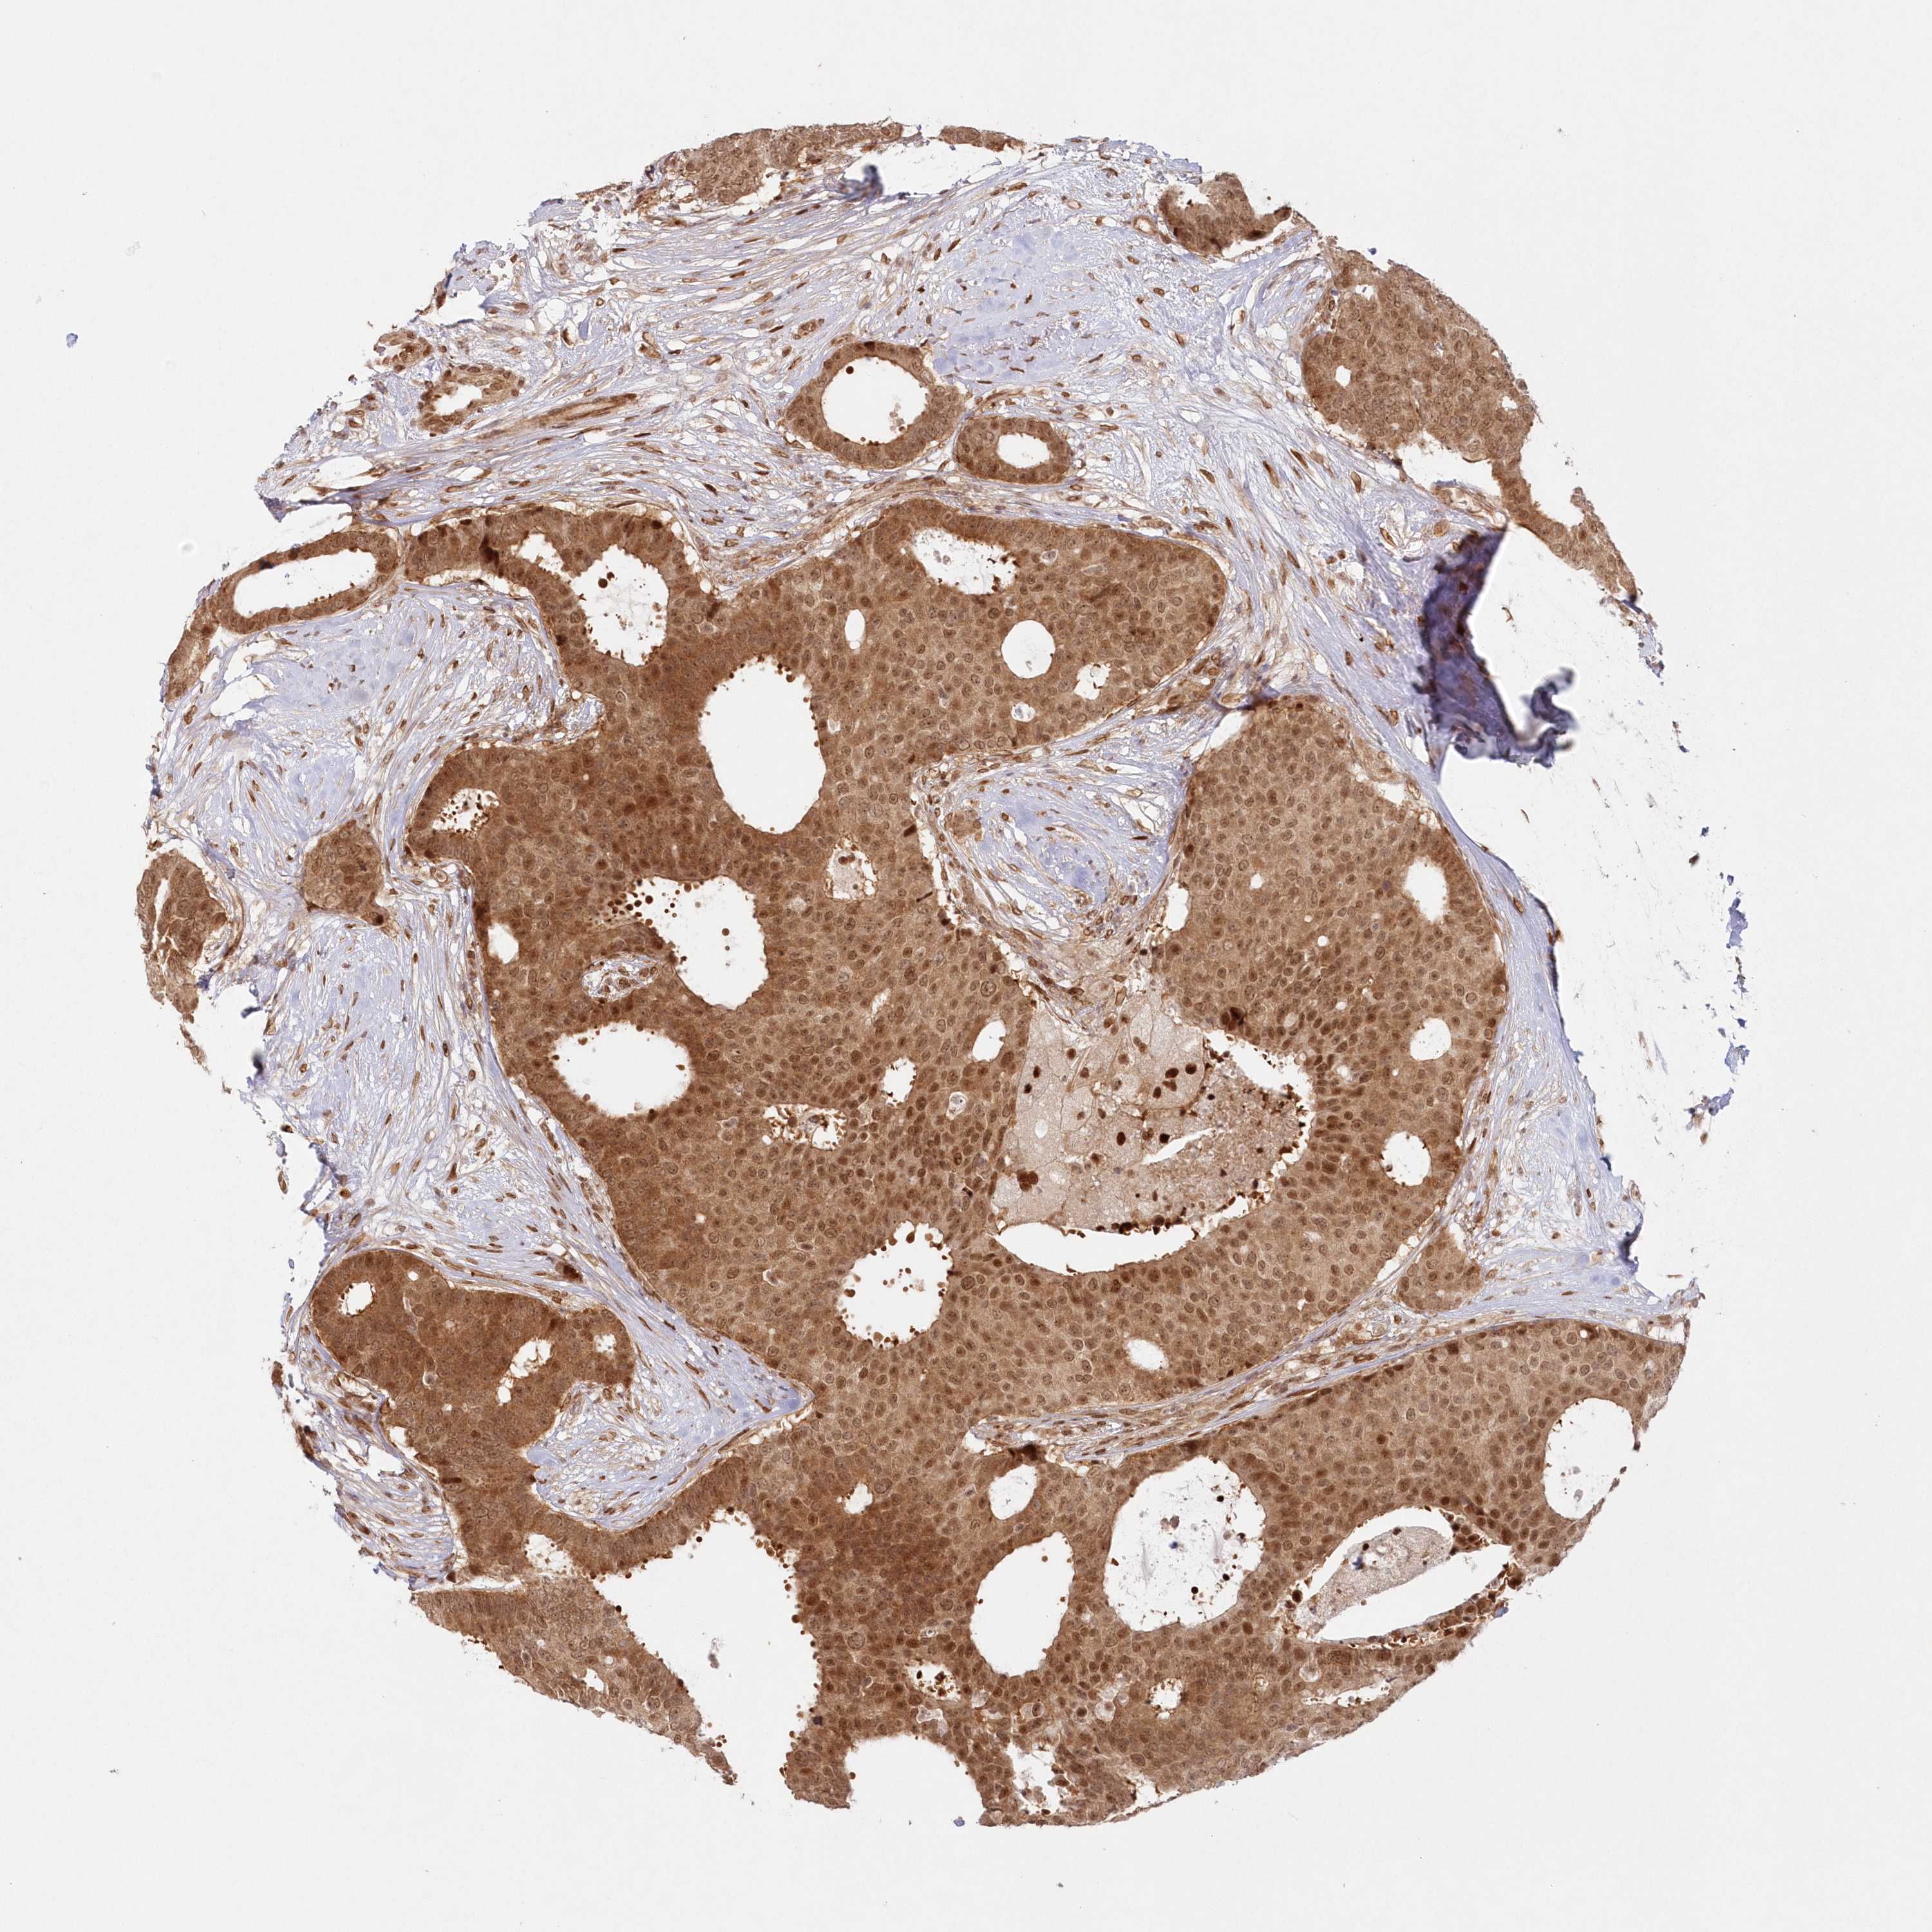

CANCER BREAST CANCER Show tissue menu

BRCA TCGA BRCA VALIDATION PROTEIN EXPRESSION

Breast cancer

Human cancer

Breast invasive carcinoma